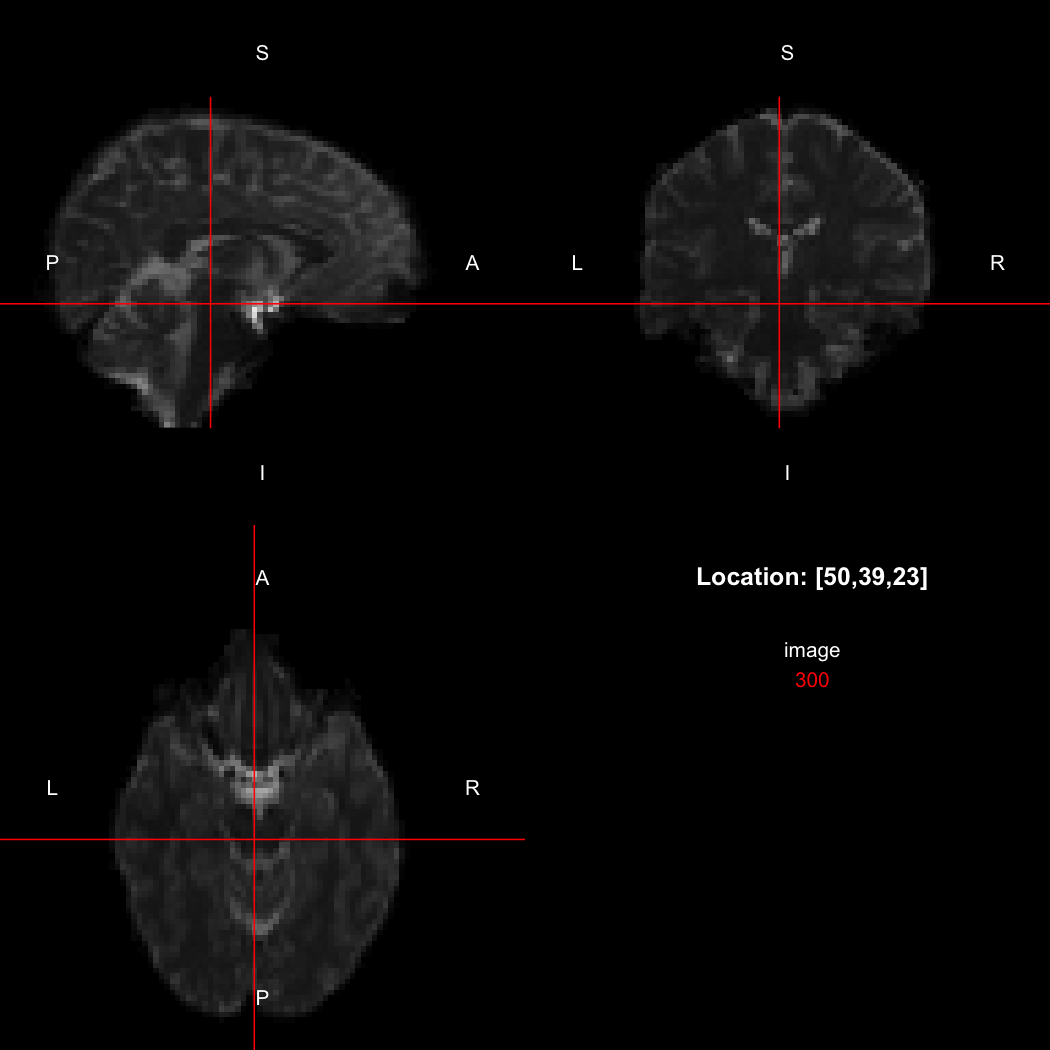

image %>% kernel_sphere(radius=3) %>% dilate() %>% subtract(image) %>% view()

## Setting window to (0, 60)

This example sets up a spherical kernel of radius 3 mm, dilates the image with it, and then subtracts the original image from the result to leave just the outer edge of the imaged object.